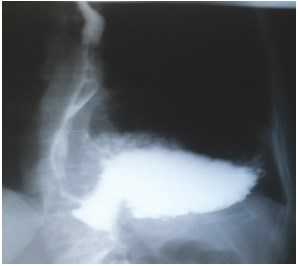

На этапе предоперационного обследования выполнялся тщательный сбор анамнеза и жалоб. Только у 6 пациентов были жалобы на изжогу, отрыжку кислым в течение нескольких лет до поступления в стационар. У больного с ущемленной параэзофагеальной грыжей и ранее имели место периодические приступы боли в грудной клетке. Жалобы на дисфагию, кашель, осиплость голоса не наблюдались ни у одного больного. Пациенты, попавшие в отделение экстренно, имели схожие симптомы при поступлении: многократную обильную рвоту, умеренные боли в животе. У двух пациентов параэзофагеальная грыжа была выявлена случайно во время планового обследования и не сопровождалась симптомами. Из инструментальных методов обследования перед оперативным лечением всем больным выполнена обзорная рентгенограмма органов брюшной полости и грудной клетки, рентгенконтрастное исследование пищеводно-желудочного перехода, водно-перфузионная манометрия пищевода с измерением давления нижнего пищеводного сфинктера, фиброгастроскопия, магнитно-резонансная томография диафрагмы (рис. 1, 2).

Рис. 2. Рентгенконтрастное исследование пищеводно-желудочного перехода в случае антральной параэзофагеальной грыжи